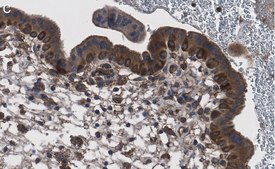

Immunohistochemistry (Paraffin) Analysis: A 1:100 dilution from a representative lot detected NF-kB p65 subunit in human placenta tissue sections.